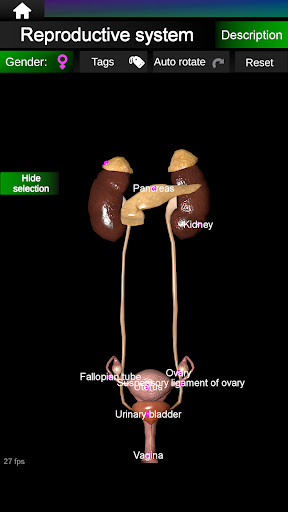

Internal Organs in 3D Anatomy لـ Vodafone Smart N9 Lite

(الأجهزة الداخلية في)

Internal Organs 3D Anatomy 3.4

يمكنك هنا تنزيل ملف حزمة تطبيق أندرويد "Internal Organs 3D Anatomy" الخاصة بجهازVodafone Smart N9 Lite مجانًا، نسخة ملف حزمة تطبيق أندرويد - 3.4 للتحميل على Vodafone Smart N9 Lite اضغط ببساطة على هذا الزر. إنه سهل وآمن. نحن نقدم فقط ملفات حزمة تطبيق أندرويد الأصلية. إذا انتهكت أية مواد موجودة في الموقع حقوقك قم بإبلاغنا من خلال